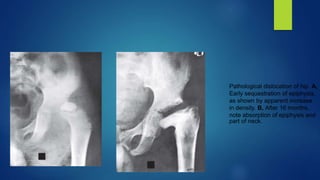

Pathological dislocation of hip. A,

Early sequestration of epiphysis,

as shown by apparent increase

in density. B, After 16 months,

note absorption of epiphysis and

part of neck.

Pathological dislocation ofhip. A, Early sequestration of epiphysis, as shown by apparent increase in density. B, After 16 months, note absorption of epiphysis and part of neck.